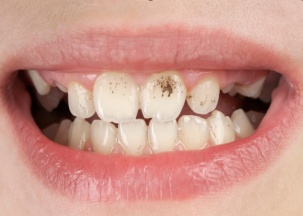

①口腔卫生较差,易长蛀牙 ②牙齿表面色素沉着